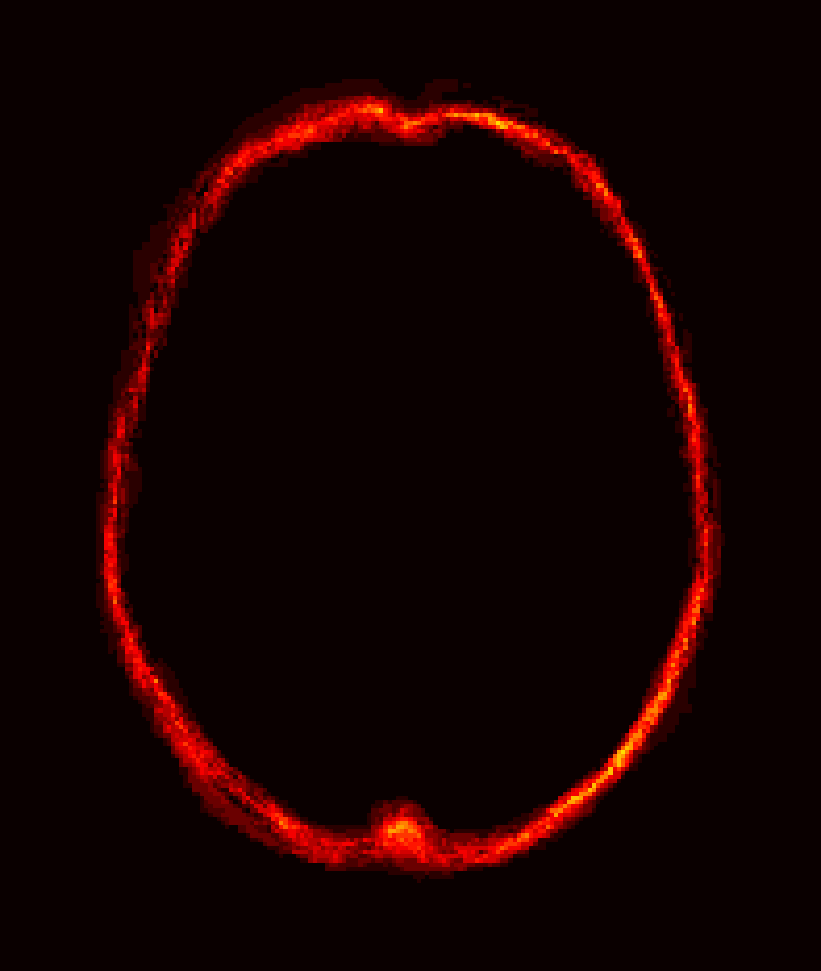

Figure 8: Example BRATS image with its decomposition result in atlas space. (a) Input image after pre-processing; (b) quasi-normal image L+M𝐿𝑀L+M; (c) non-brain image S𝑆S; (d) pathology image T𝑇T.

In addition to extracting the brain from pathological datasets, our method also allows for the estimation of a corresponding quasi-normal image in atlas space, although this is not the main goal of this paper. Fig.8 shows an example of the reconstructed quasi-normal image (L𝐿L) for an image of the BRATS dataset, as well as an estimation of the pathology (pathology image T𝑇T and non-brain image S𝑆S). Compared to the original image, the pathology shown in the quasi-normal image has been greatly reduced. Hence this image can be used for the registration with a normal image or a normal atlas. This has been shown to improve registration accuracy for the registration of pathological images [27]. Furthermore, an estimate of the pathology (here a tumor) is also obtained which may be useful for further analysis. Note that in this example image the total variation term captures more than just the tumor. This may be due to inconsistencies in the image appearance between the normal images (obtained from OASIS data) and the test dataset. As our goal is atlas alignment rather than quasi-normal image reconstruction or pathology segmentation, such a decomposition is acceptable, although we could improve this by tuning the parameters or applying regularization steps as in [27].